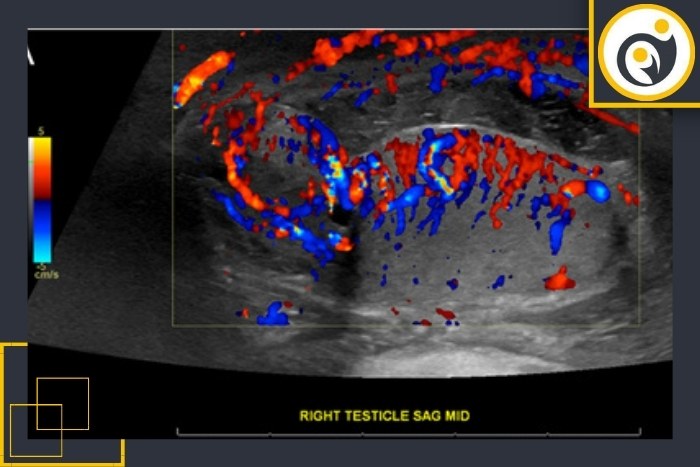

پزشکان برای تشخیص دقیق تورشن بیضه از سونوگرافی داپلر رنگی (Color Doppler Ultrasound) استفاده میکنند.

این روش تصویربرداری نه تنها تصویر ظاهری بیضه را نشان میدهد بلکه جریان خون داخل بیضه را نیز بررسی میکند.

در حالت طبیعی:

بیضه سالم باید جریان خون منظم و قابل مشاهده در تصویر داشته باشد.

در حالت پیچخوردگی:

به دلیل چرخش طناب اسپرماتیک جریان خون تقریباً قطع میشود یا بسیار کاهش مییابد؛ در نتیجه در تصویر هیچ رنگ یا حرکت جریان دیده نمیشود.